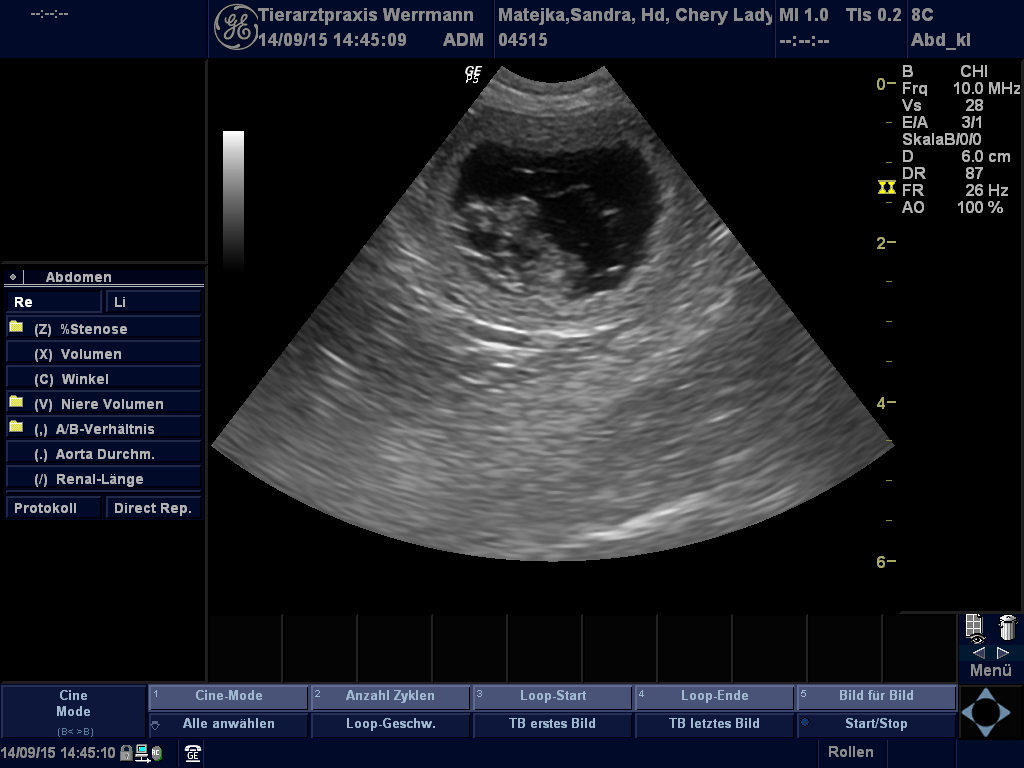

Ultraschallbilder